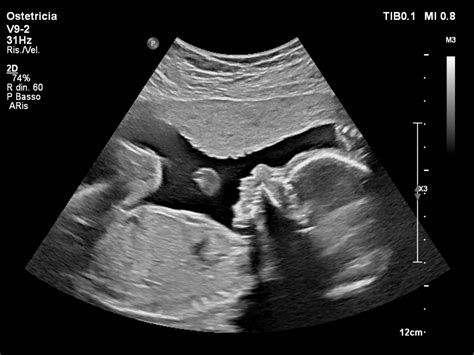

Translucenza Nucale (TN): Questo test ecografico misura lo spessore della plica cutanea nella regione nucale del feto. Un aumento della translucenza nucale può essere indicativo di un rischio maggiore di anomalie cromosomiche, come la sindrome di Down. La TN viene comunemente eseguita tra l'11ª e la 14ª settimana di gestazione. Sebbene valori elevati possano essere associati a condizioni genetiche, è importante sottolineare che la TN non fornisce una diagnosi certa, ma piuttosto indica la necessità di effettuare indagini più approfondite.